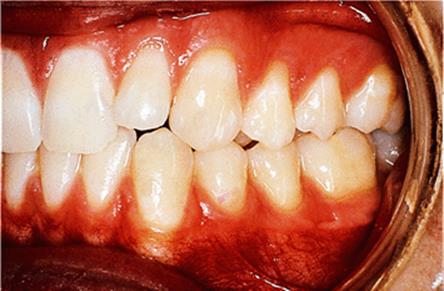

The appliance holds the mandible in a forward postured position, in this case with the incisors edge to edge (Fig. 18.1(f)). The facial musculature is thus stretched, and applies a posterior force to the upper arch and an anterior force to the lower arch. The lower incisors have acrylic capping to prevent excessive labial tilting of the lower incisors, and this also serves as a bite-plane to reduce the overbite (Chapter 10). The appliance must be worn for at least 14–16 hours each day, but once the overjet has been reduced fully the amount of daily wear can gradually be reduced to sleeping hours only. The patient should continue to wear the appliance overnight in this way as a retainer, at least until the period of rapid pubertal growth is complete. Figures 18.1(g) and 18.1(h) show the dental and facial changes which occurred during treatment.

Fig. 18.1. (a) This 12-year-old girl had a skeletal II facial pattern and average facial proportions. The lips were incompetent with the lower lip lying below the upper incisors at rest. (b), (c) She had a Class II division 1 malocclusion with an overjet of 10 mm, the overbite was increased and complete, and the molar relationship was Class II on both sides. (d), (e) The upper and lower arches were well aligned. (f) A functional appliance (an activator) was fitted. (g) The corrected occlusion with Class I incisor and molar relationships. (h) The patient's facial profile at the end of treatment.